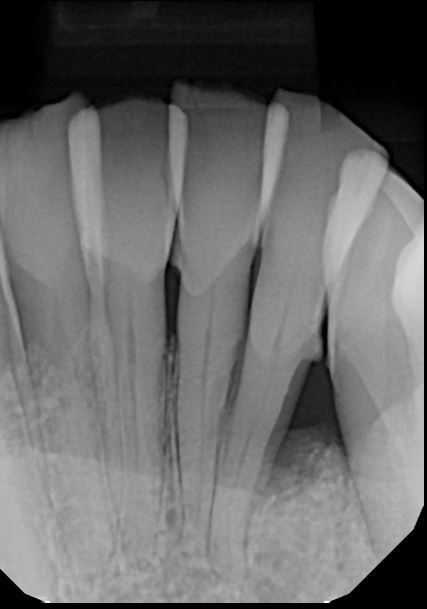

Dental assistants can take intraoral images of a patient’s chief areas of concern prior to the dentist entering the treatment room. For example, a patient of record presents with a fractured lingual cusp. The assistant takes a radiograph of this area, which will offer 1 view of the tooth, whereas the intraoral image will give a clear view of the exact depth of the fracture.

Once the doctor evaluates the tooth, they can explain the necessary treatment, showing the patient both the radiograph (which many patients may not understand) and the clinical image. Dental assistants may use the camera to take initial arch records for the patient’s chart.